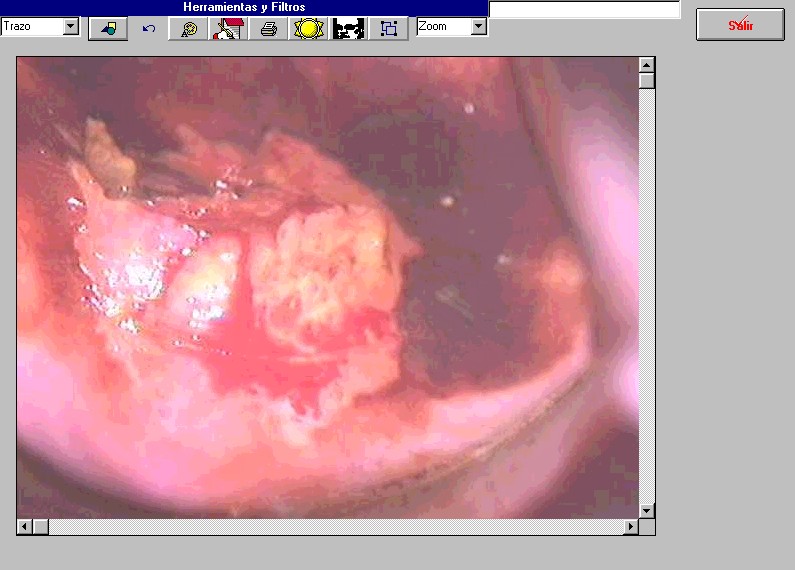

Colposcopía Digital

colpodoc3.jpg (82449 bytes)